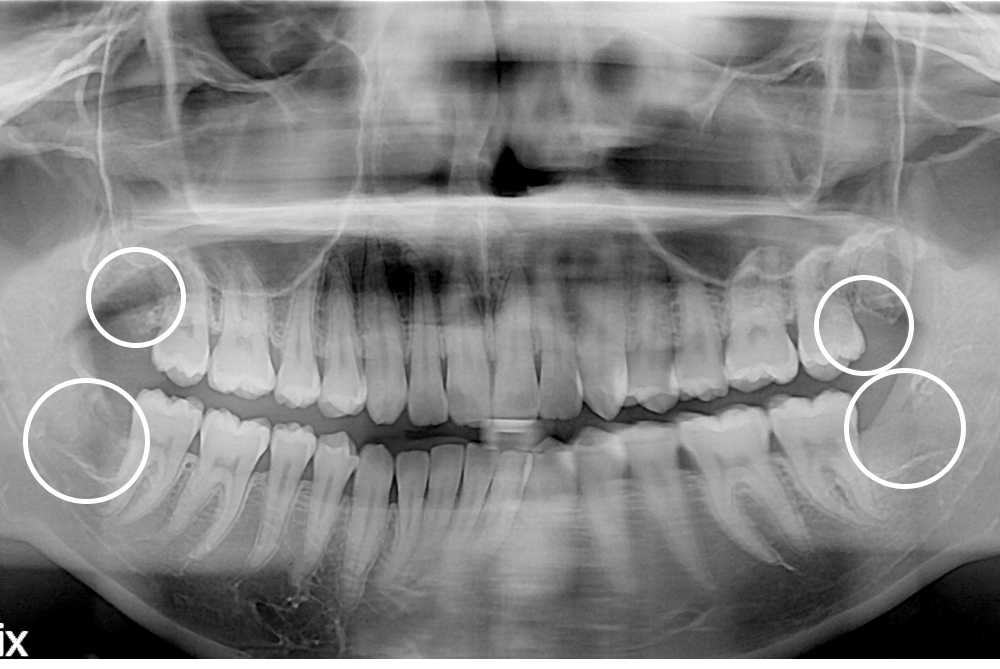

치료후 : 2017-12-28

세종치과는 구강악안면외과학 박사이신 원장님이 발치하는 치과입니다.